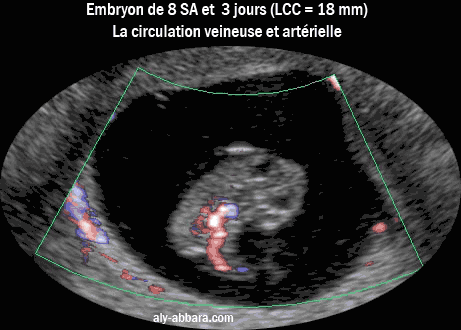

Image échographique analysant la circulation sanguine veineuse et artérielle chez

un embryon de 8,5 semaines d'aménorrhée (6 semaines et 3 jours de gestation)

Cette analyse est possible grâce à la nouvelle technologie Doppler (Dynamic Flow)

Analyse de la circulation embryonnaire veineuse et artérielle à 8,5 SA